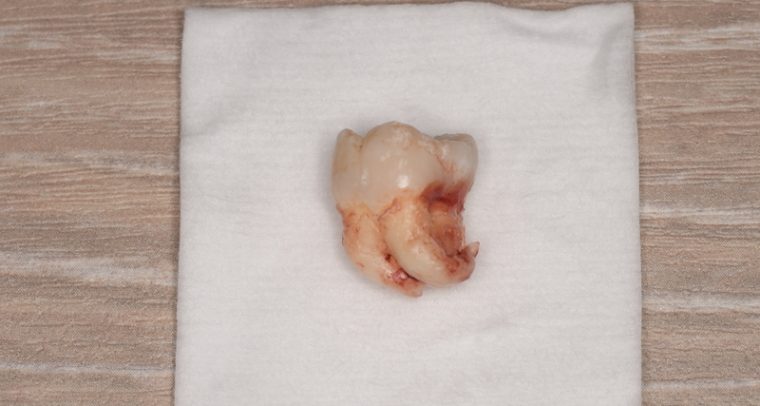

CASE 2

| 抜歯費用 | 約2,500円(保険内) 別途CT撮影で3,000円 |

| 抜歯内容 | 左上下の親知らず抜歯 |